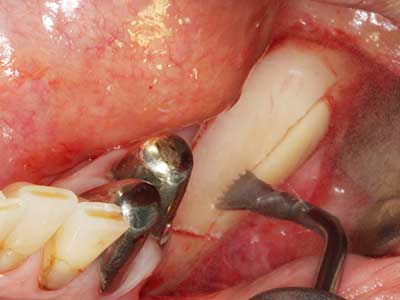

Когато се извършват хирургични процедури върху кост в непосредствена близост до чувствителни структури като кръвоносни съдове или нерви, ротиращите инструменти създават значителен риск за ятрогенно нараняване. Пиезоелектрическите апарати могат да бъдат от помощ при препарация на костно покритие и отстраняване на твърда кост близо до нерви, особено за оголване на нервите след ятрогенно нараняване, както и по време на латерализация на нервите за резекционни и реконструктивни процедури или поставяне на имплант (Фиг. 17-20). Лекият контакт между пиезонакрайника и нерва по принцип не води до нараняване, но ако действате непредпазливо с трионообразни движения или приставки за остатъчен костен субстрат, може да причините временно или перманентно увреждане на нерва. Въпреки това, рискът от увреждане се счита за много по-малък, отколкото при употреба на триони или ротиращи инструменти (Pereira, Gealh et al. 2014).